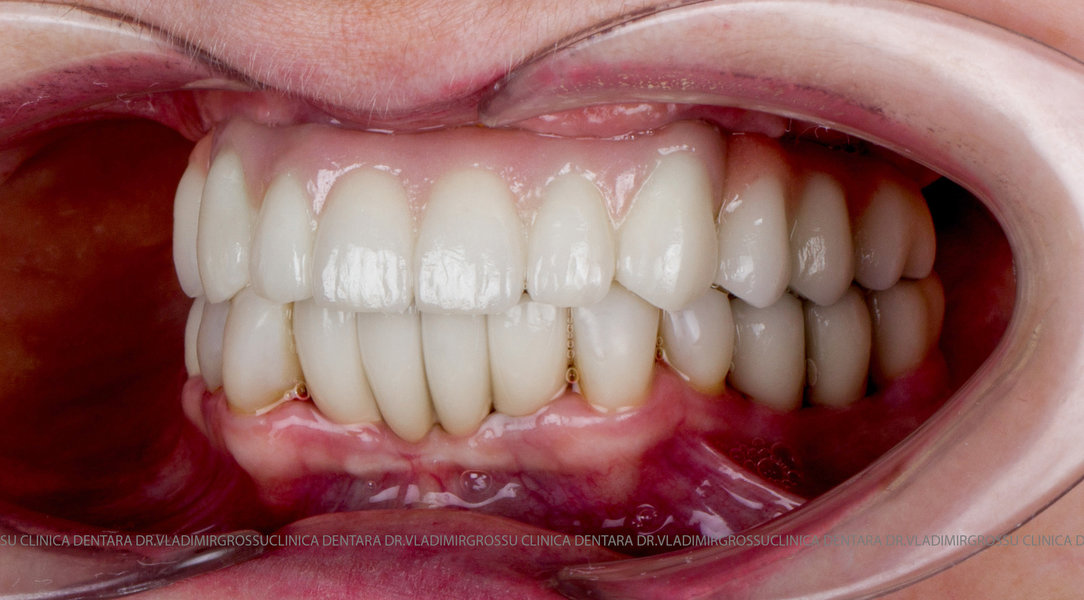

Cazuri clinice conceptul All-on-6